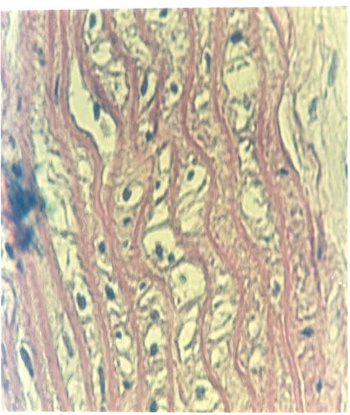

The aortic intima of methionine treated rats (Met) which have been fed 200mg methionine, showed degeneration and desquamation of endothelial cells. Degenerative alterations were observed also in the media. In contrast to control animals, whose aortic sections have chromatic-rich, predominantly elongated to spindle- or comma-shaped mediocyte nuclei (fig. 1-A), the aortas of the experimental animals exhibited after 4 wk methionine treatments, bright cytoplasm and enlarged, bright, round to oval, often radially arranged nuclei of a majority of the mediocytes. Dissolution of single mediocytes with karyolysis is observed not infrequently and appears to lead to the formation of tissue gaps which appear optically empty (fig. 1-B).

Simultaneous administration of methionine and cholesterol over a long period of time (4 wk) yielded no exacerbation of the alterations produced by methionine alone (fig. 1- C). By light microscopy, these methionine induced alterations of aorta showed considerable morphological similarity to the alteration detected by Matthias and al [4].

Fig. 1: Representative cross section stained with Hematoxylin-eosin through the abdominal aorta of the control, Met, Chol, and Met-C groups

A- morphology of smooth muscle cells of media. Dark chromatin rich, predominantly longish to spindle -shaped nuclei running parallel to the circumference. B- endothelial cells largely retained. Mediocytes with predominantly bright cytoplasm and mostly bright oval, often radially arranged nuclei, near cells with dark pyknotic nuclei. Scattered karyolysis with incipient formation of tissue gaps. The number of media nuclei appeared reduced. C- Considerable morphological similarity to alterations induced by methionine. (X1300).